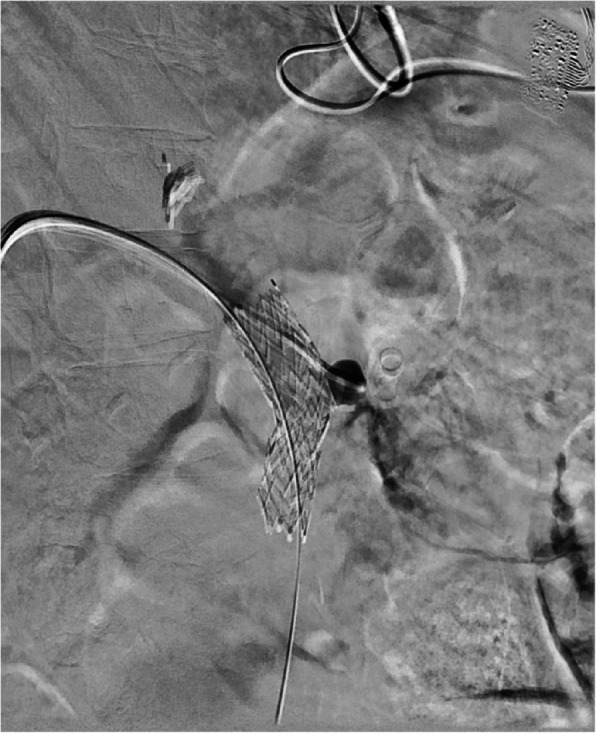

This case describes the endovascular treatment of a 55-year old female with a ruptured portal vein pseudoaneurysm secondary to a large stomach ulcer resulting in massive active hemorrhage into the adjacent stomach. This patient presented with persistent hypotension secondary to chronic GI blood loss and simultaneous septic shock. After an abrupt drop in blood pressure, the patient arrived in the angiography suite where the ruptured pseudoaneurysm was apparent on portal venogram. Emergent stent assisted coil embolization was performed to stabilize the patient and treat the portal vein pseudoaneurysm. To our knowledge, this case presents the only portal vein pseudoaneurysm secondary to a gastric ulcer.Level of Evidence Level 4, Case-report.

Abstract Image